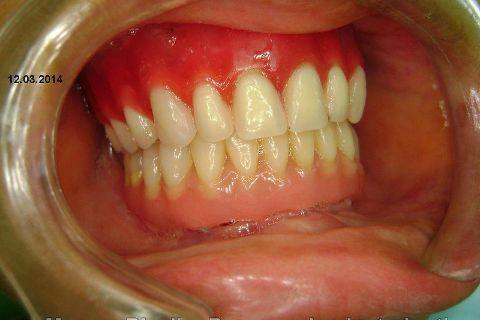

Fase Protética da Reabilitação em Maxila Atrófica

Atualização do caso clínico que já postei, "REABILITAÇÃO EM MAXILA ATRÓFICA COM IMPLANTES", um caso que inclui expansão do rebordo estreito com cinzel e martelo, expansores rosqueáveis, enxerto e instalação dos implantes distais inclinados tangenciando seio maxilar. Inclui esvaziamento do forame nasopalatino e preenchimento com biomaterial para instalação de dois implantes próximos dele. Cirurgia realizada em única sessão, com instalação dos 6 implantes. Para os colegas que não conheceram e/ou esqueceram da apresentação, este é o resumo do caso na fase cirúrgica.http://www.youtube.com/watch?v=BtvexFexRPA&hd=1

FASE PROTÉTICA DA REABILITAÇÃO EM MAXILA ATRÓFICA...incluindo a reabertura, instalação dos minipilares e PTR provisória reembasada sobre os cilindros de proteção.

Fotos do caso